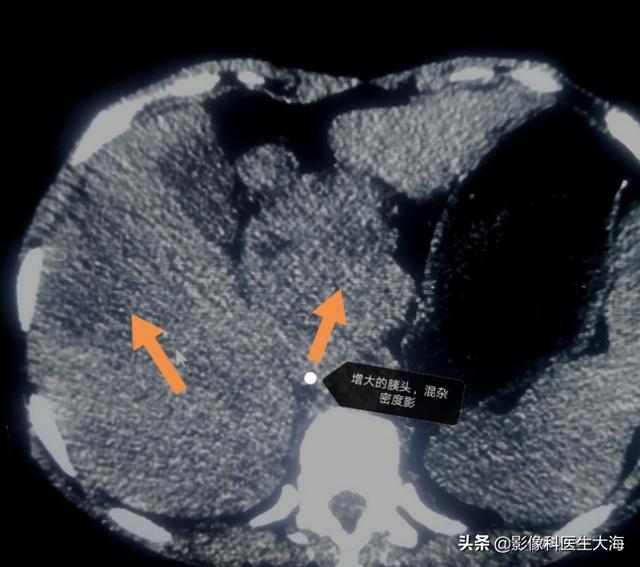

私はイメージングの医師の海、定期的にプラスああ注意のような健康の知識を共有しています!